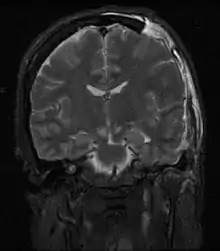

颅内压 (ICP,Intracranial Pressure)是指颅骨内部脑组织和脑脊液(CSF,Cerebrospinal Fluid)中的压力。颅内压的测量单位是毫米汞柱(mmHg),其成年人正常值在平卧姿势安静状态时为7-15 毫米汞柱。[1] 正常人体可通过各种调节机制来维持颅内压的稳定,一名正常成年人通过调整CSF分泌和吸收平衡可以将颅内压的波动范围稳定在1毫米汞柱内。ICP的变化可由颅骨中某一种或多种组织结构变化所导致的容量变化引起。 同时,脑脊液的压力也可受到其他各种因素的影响,如:突然改变的胸腔及腹腔压力变化。

颅内压增高(常见缩写 IH, IICP 或 raised ICP)指颅骨内增高的内容组织压力。颅内压正常值为7到15 毫米汞柱,其最高正常限值为20-25 毫米汞柱,异常增高的颅内压需接受降低颅内压治疗。[2]